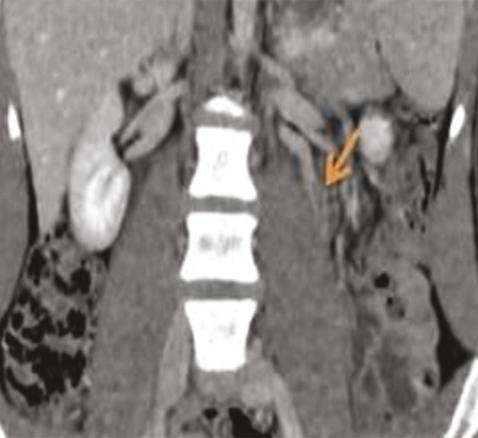

La tomodensitométrie (TDM) a montré une dilatation de la veine rénale de 9 mm, en amont de la pince aortomésentérique (fig. 1) et un matériel hypodense au niveau de la veine spermatique homolatérale, en rapport avec un thrombus (fig. 2).

La tomodensitométrie (TDM) avec injection de produit de contraste objective cette compression de la veine rénale gauche dans la fourchette aortomésentérique, l’angulation entre l’aorte et l’artère mésentérique supérieure (supérieure à 41 °), la distension des veines gonadiques et la congestion pelvienne.2